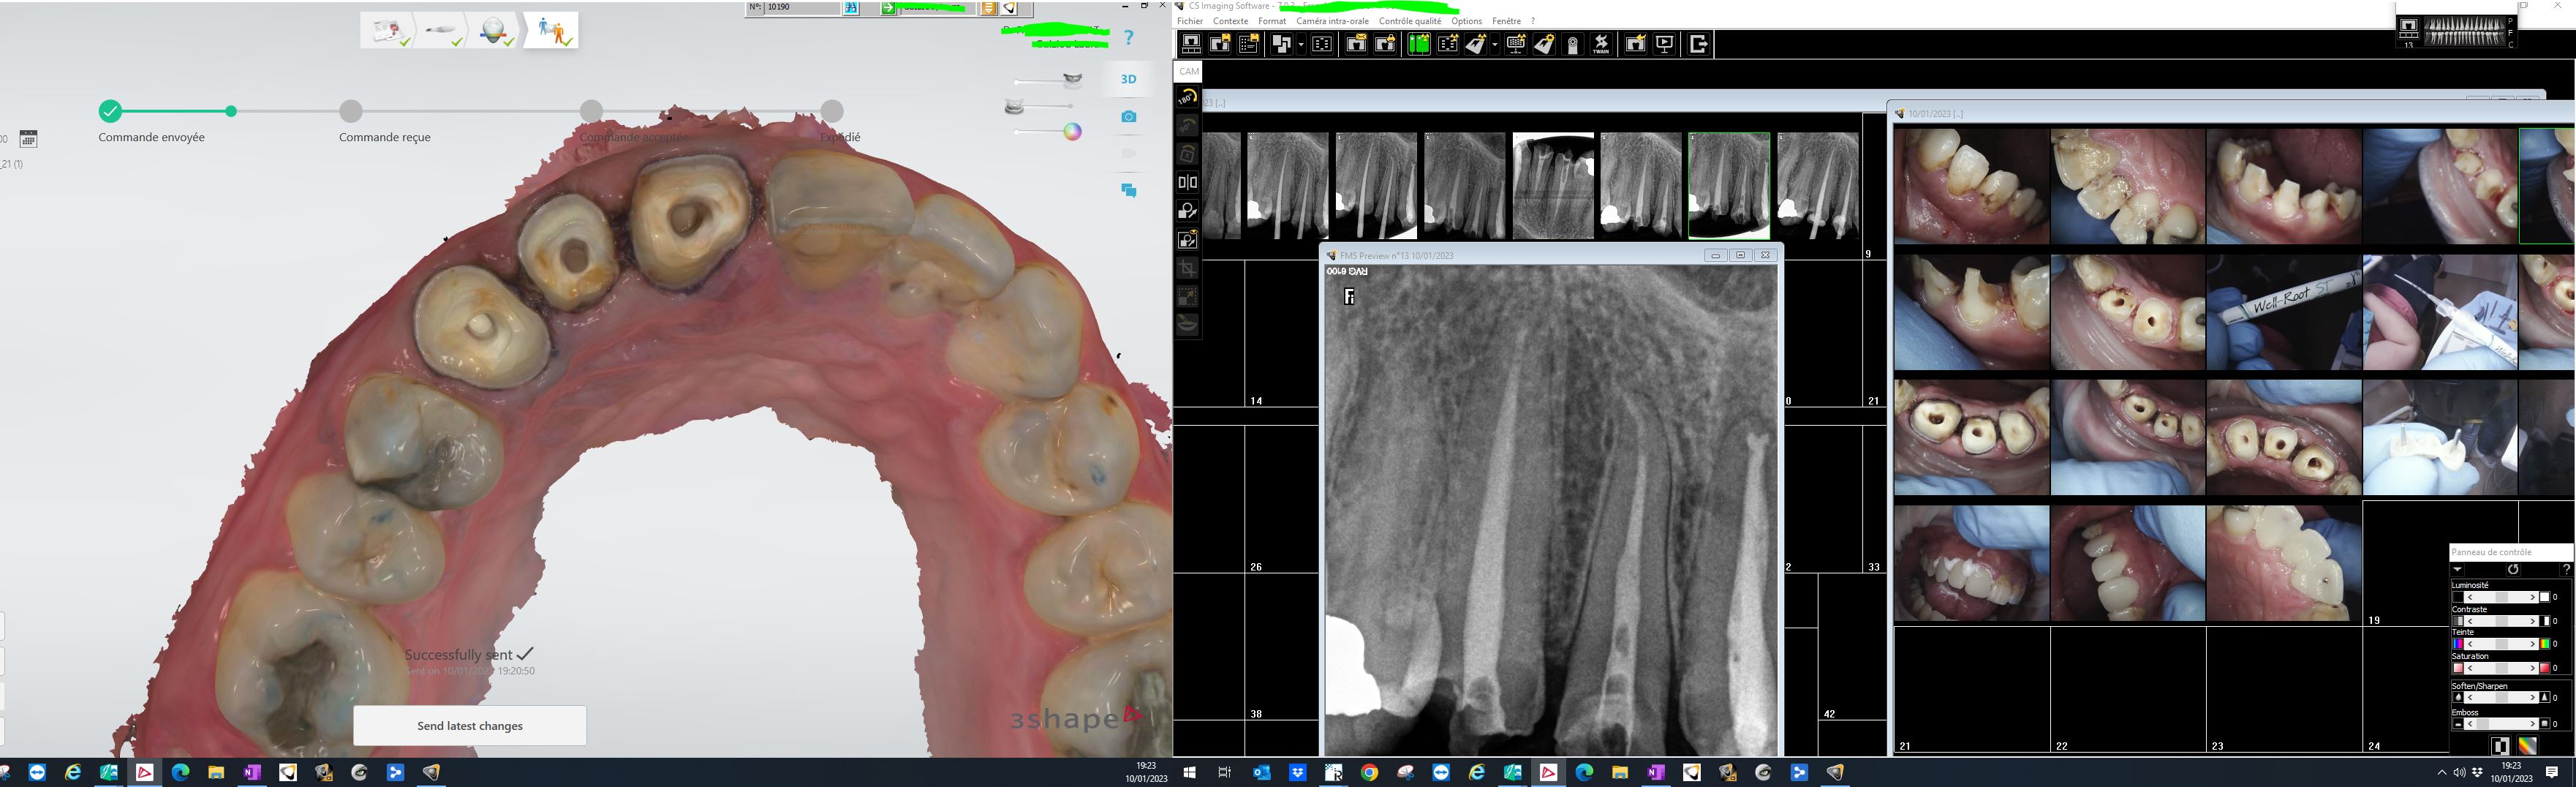

Bio ceram monocone.

ca fait plaisir de revoir les photos de chicot29 :))

on peut s'apercevoir que les temps changent, il fait même plus d'inlay core !!!!

Ben ils peuvent toujours évoquer. Ca va etre dur à partir d'une radio de déterminer quel type de méthode d'obturation a été utilisée. Par contre des défauts d'obturation ça il y en a un paquet vu le tarif payé c'est pas étonnant.

Radio bio ceram en place. Je t'en collerais moi de la flotte. -)

je pense que les dentistes qui prennent autant de radio per-op pour l endo ne sont pas sûr de ce qu ils font... ;)

Ne jamais avoir de certitudes. J'aime bien que la bio ceram aille à l'apex avant de sceller le cône.